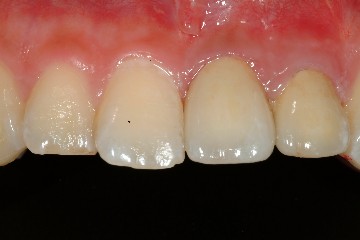

圖十八、十九為技師所完成的全瓷冠成品,氧化鋁全瓷冠有輕微透光性,可將牙齒的金屬釘柱遮光,但色澤與自然牙齒相仿,是牙科2000年後的最新科技發展。圖二十為裝牙齒前的情況,經試戴、調整、及黏著後,過了一週,病患回診所的結果(圖二十一、圖二十二),經過全瓷冠的修復,患者得到滿意的結果,可以再度露出自信且迷人的笑容了。

圖二十一 |

圖二十二 |